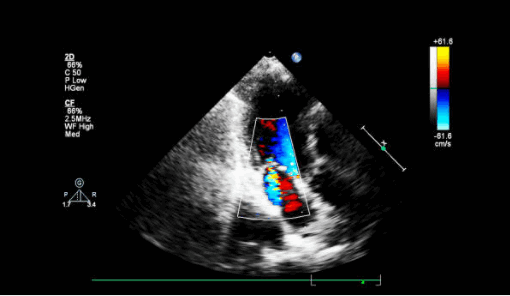

- Поместите цветной допплеровский сектор на митральный клапан и левое предсердие. Посмотрите есть ли струя митральной регургитации (высокоскоростной или турбулентный пятнистый поток в систоле)? Во многих случаях он будет направлен эксцентрически либо к передней, либо к задней стенке левого предсердия. Как правило, молотящая створка МК направляет струю MР в сторону от самой поврежденной створки.

- Повторите двумерное (2D) изображение и цветное допплеровское сканирование митрального клапана в апикальном четырехкамерном и апикальном трехкамерном срезе. По техническим причинам низкое качество изображения нередко препятствует абсолютному определению того, есть ли молотящая створка МК, но есть эксцентрическая струя значимой МР или хордальная структура, колеблющаяся в левом предсердии проксимальнее митрального клапана, что повышает вероятность разрыва митрального аппарата.

Другой причиной внезапной артериальной гипотензии и отека легких у пациента в пери- и постинфарктном периоде является разрыв межжелудочковой перегородки. Дефект заставляет насыщенную кислородом кровь течь из левого желудочка в правый и смешиваться с деоксигенированной кровью. Дефекты межжелудочковой перегородки (ДМЖП) могут возникать в переднем отделе перегородки (лучше всего видно в парастернальных окнах) из-за переднего ИМ или в нижнем отделе перегородки (лучше всего в апикальном четырехкамерном и субкостальном окнах) в результате нижнего ИМ. Оба типа ДМЖП могут быть проверены на предмет использования парастернальных окон по короткой оси. Использование цветного допплера имеет важное значение для обнаружения этих разрывов на эхокардиографии, потому что разрыв ткани часто имеет щелевидную или змеевидную форму и может быть плохо заметен на одном только 2D-изображении.

- Поместите цветное допплеровское окно на межжелудочковую перегородку, особенно на любые акинетические участки или сегменты с пропаданием эхо-сигнала (анэхогенные зоны). Цветовой поток слева направо, проникающий через перегородку, указывает на ДМЖП.